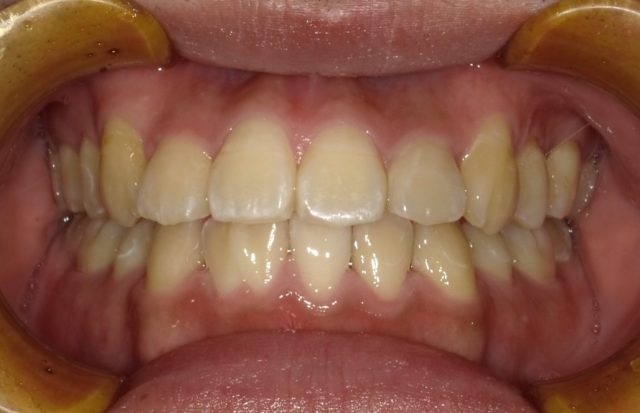

【正面観】

【before ⇨ after】

| 主訴 | 前歯のガタガタ |

|---|---|

| 診断名 | 前歯部叢生を伴う下顎前突 |

| 初診時年齢・性別 | 7歳10ヶ月・男児 |

| 治療期間 | 1段階目:2年3ヶ月 経過観察:6年 2段階目:1年5ヶ月~ |

| 治療方法・治療内容 | 4本抜歯・フルブラケット・ストレートワイヤーテクニック |

| 費用 | 1段階目検査診断料¥315,00 1段階目矯正基本料¥315,000、調整料¥113,400 経過観察料¥11,000 2段階目検査診断料¥5,500 2段階目矯正基本料¥440,000 調整料¥121,000~ |

| デメリット・注意点 | 抜歯が必要・硬い物や大きい物など食事への配慮 |